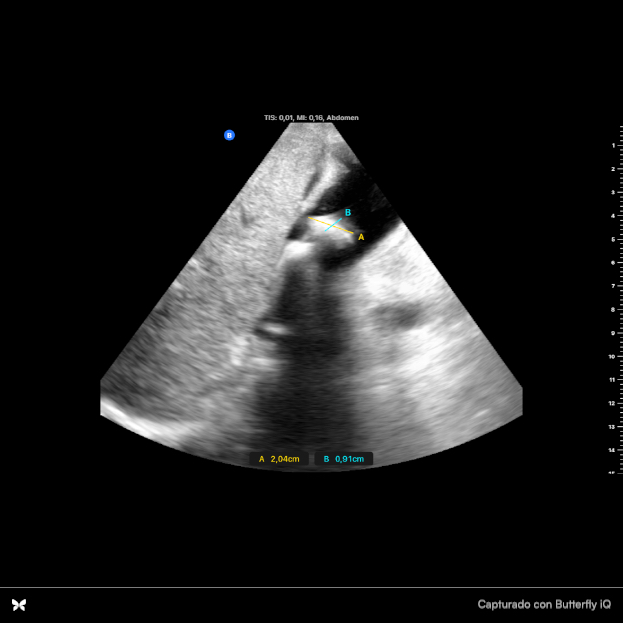

Se observan dos imágenes hiperecoicas en infundíbulo de vesícula que dejan sombra acústica posterior, una de ellas de 2 cm x 0.94 cm con aumento de grosor de vasos suprahepáticas. Parénquima hepático sin alteraciones. Se observa espacio anecoico superior al diafragma. Resto sin hallazgos.